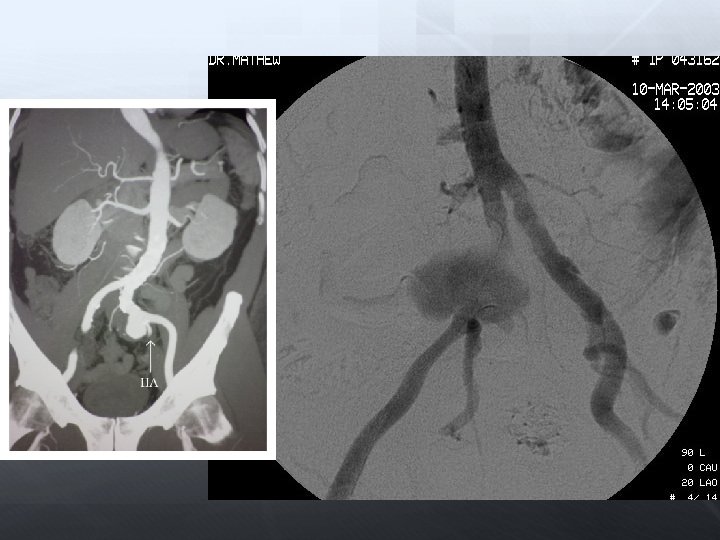

Darlık Oklüzyon Aorto-iliak Femoral-popliteal Infrapopliteal

Aorta-İliak

Her zaman laboratuarda bulundurulmalı Rüptür için Anevrizma AV fistül